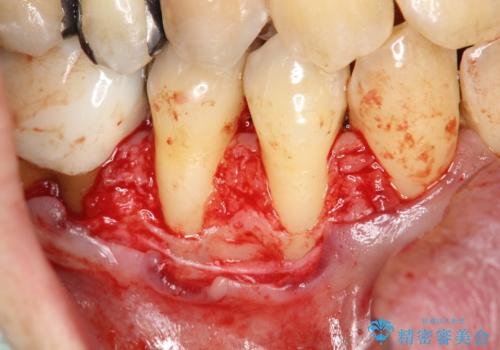

今回のケースでは小臼歯2本分の幅に渡って丈夫な歯肉を確保させるため、オペのデザイン上、横に幅広く均一な結合組織を採取する必要がありました。そのため、トラップドア方式で内部の組織をえぐって採取する術式は使わず、上顎歯肉の表層から結合組織部までを含む部分までを遊離歯肉採取の要領でやや深めに採取し、表層部分をトリミングする事で均一な厚みの結合組織を採取しました。この術式の利点として、上顎の歯肉に過度に深い侵襲を与える事がないため、組織採取部の術後の治癒が非常に早く、術後の不快症状も少なくて済む事が挙げられます。